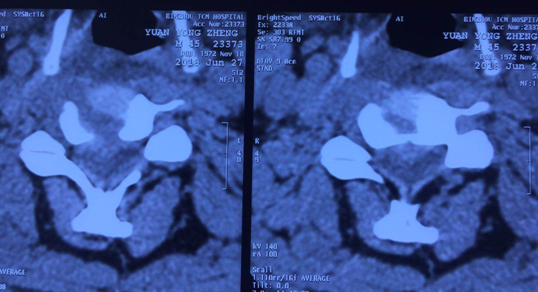

术后CT